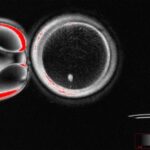

Яйцеклетка с ядрами клеток кожи человека до оплодотворения.

Согласно новому исследованию, ученые использовали кожу человека для создания оплодотворяющих яйцеклеток, способных производить ранние эмбрионы, что может увеличить возможности лечения бесплодия. В ходе исследования, опубликованного во вторник в журнале Nature Communications, была взята ядро, часть клетки, которая содержит большую часть генетической информации, из обычной кожи человека и пересажена в донорскую яйцеклетку, практически не имеющую собственного ядра. Исследователи вызвали 82 человеческих яйцеклетки, или незрелые яйцеклетки, которые затем подверглись оплодотворению в лаборатории. Результат — яйцеклетка, ДНК которой соответствует ДНК человека, дающая клетки кожи, и которая может быть оплодотворена спермой другого человека, — является важной вехой в разработке нового протокола борьбы с бесплодием, хотя пройдет не менее десяти лет, прежде чем этот метод получит клиническое применение. «Доступно», по словам доктора Паулы Амато, соавтора исследований и профессора акушерства и гинекологии медицинского факультета OHSU. «Этот результат был бы пожилым в женское время или в женщине, не способный яйцеклеток по какой-либо причине (например, ранее лечившимся от рака), иметь генетически связанного ребенка», — написала Амато по электронной почте. «Кроме того, это может привести к однополым парам (например, к мужчинам) иметь ребенка, связанного с генетическими заболеваниями с обоими руководителями».